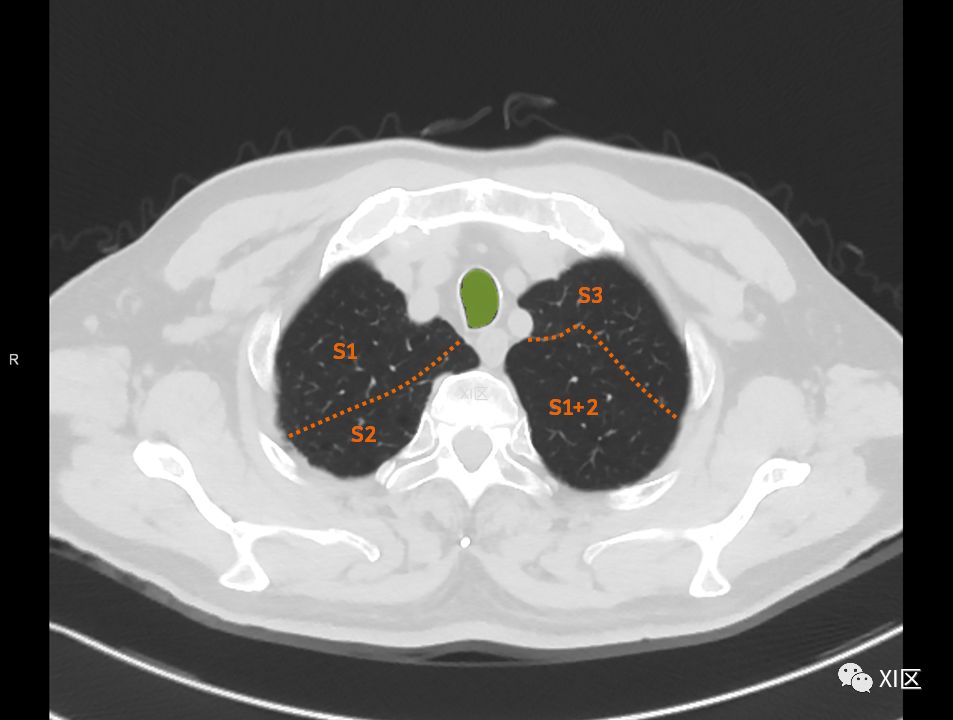

横断位

肺的分段

肺的断层分段示意图

在进行肺的分段时,可以上下观察浏览,沿着相应气管的走形可以更容易准确地进行分段。